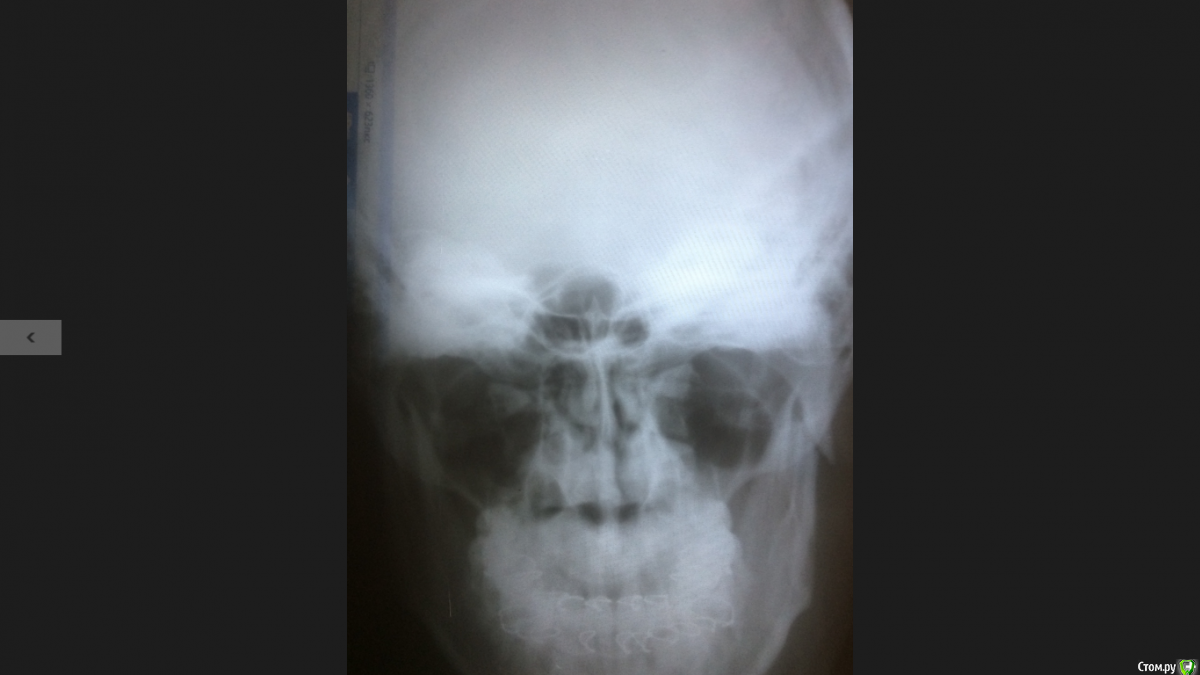

Как то Так Опубликовано 12 декабря, 2017 Автор Поделиться Опубликовано 12 декабря, 2017 Прошу прощения за не надлежащее выполнения требований данного форума,не мог разобраться как выложить снимки ,ну вот что то получилось) посмотрите пожалуйста .... Ссылка на комментарий

Irouil Опубликовано 12 декабря, 2017 Поделиться Опубликовано 12 декабря, 2017 Диастаз приличный, но с 27.11 уже репозицию (сопоставление) без остеотомии (нового, хирургического перелома) не провести, так что ждите результатов. Через месяц после перелома сделаете снимок, на его основании и можно будет решать. Шансы на успешное заживление есть. 1 Ссылка на комментарий